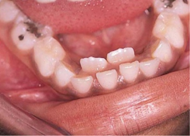

Πρόκειται για μια κατάσταση, που συμβαίνει αρκετά συχνά, ιδιαίτερα στα κάτω μπροστινά δόντια, όπου τα μόνιμα ανατέλλουν πίσω από τα παιδικά δόντια, χωρίς αυτά να κουνιούνται. Μην ανησυχείτε και προσπαθήστε να κουνήσετε αρκετά τα παιδικά δόντια ώστε αυτά να “ βγουν ” από μόνα τους. Εάν αυτό δεν είναι εφικτό θα πρέπει να γίνει η εξαγωγή των παιδικών δοντιών από τον παιδοδοντίατρο, ώστε τα μόνιμα δόντια να έρθουν μπροστά στη θέση τους με τη βοήθεια της γλώσσας.